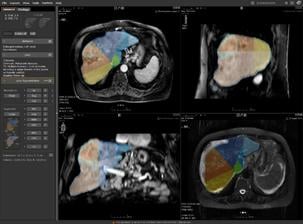

MRI is a vital imaging tool for the evaluation, assessment and management of the liver. CADstream’s liver application features include automated 3D image registration, segmentation (including whole organ, Couinaud-segments and lesion segmentation), kinetic and diffusion-weighted imaging analysis, patient monitoring comparisons and reporting. With CADstream, clinicians have a solution to automate analysis and standardize interpretation, ultimately achieving higher quality imaging studies, lower costs for radiology practices and improved communication for physicians and patients. Merge CAD will also showcase the latest in CADstream’s breast and prostate applications at RSNA 2009.